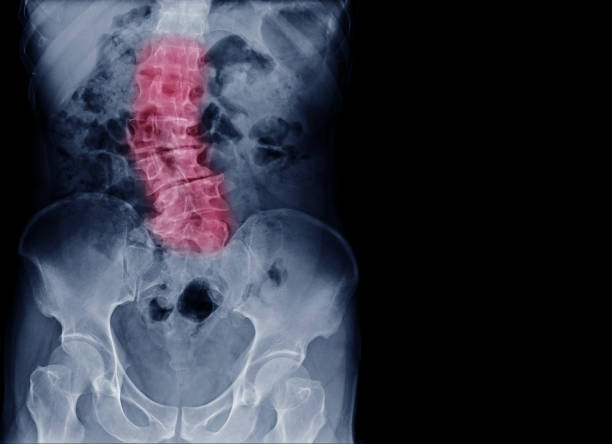

Como ves en esta ilustración, cada vertebra desalineada puede producir una molestia, desequilibrio o convertirla en crónica.

Estas vertebras desalineadas presionan los nervios, y el sistema nervioso resentido produce todos estos desequilibrios:

Cada una de las vertebras influye en los órganos que rodean su zona, como puedes comprobar en esta imagen.

Quizás esto te de pistas de lo que te este pasando.